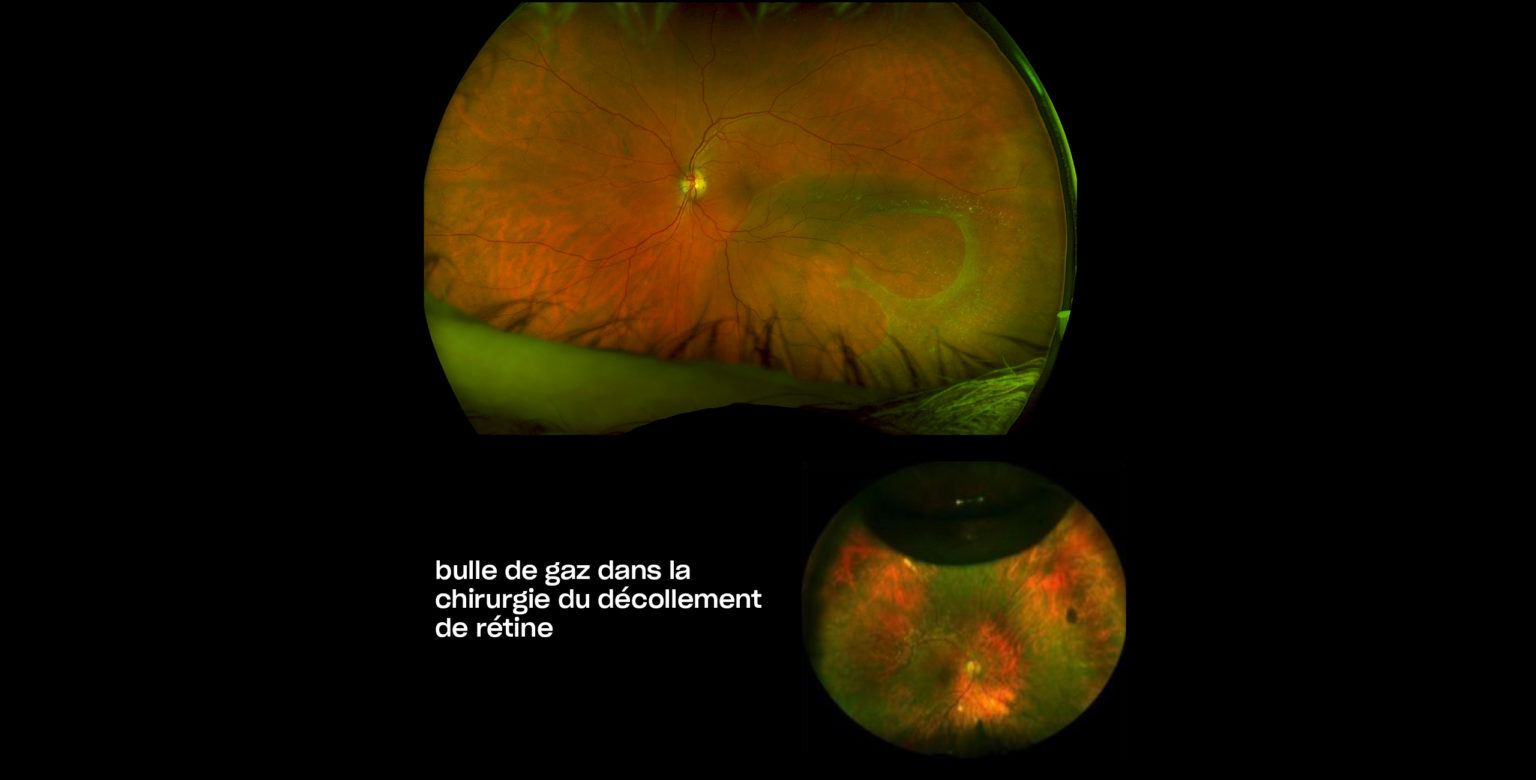

ophtavalmy.frFond D’oeil_Décollement Rétine Supérieur Avec Déchirure Rétinienne

ophtavalmy.frFond D’oeil_Décollement Rétine Supérieur Avec Déchirure Rétinienne